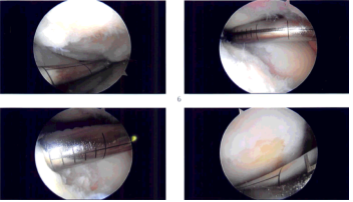

There was a Grade IV defect of the medial femoral condyle which was debrided with the use of curette and debrided, and abrasion chondroplasty was performed with the use of a curette. The defect was measured and was 1.5 cm by 1.5 cm. Examination revealed an intact ACL.

The examination noted lateral tibial tendon patellofemoral compartment showed intact cartilage. Examination of the patellofemoral compartment showed intact cartilage over the patella but there was Grade III to Grade IV osteochondral lesion of the trochlea.

Debridement of this lesion was performed to stable margins. The defect was measured to be 1.5 cm x 1 cm. All the measurements were taken. All the pictures were taken and saved.

Intraoperative Arthroscopy Images